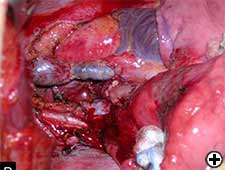

Tumors involving the carina or right tracheo-bronchial angle may involve the superior vena cava (SVC), either directly or by nodal extracapsular infiltration. In these cases, a combined surgical procedure is mandatory and represents a challenging operation because in addition to the technical complexity, each procedure requires contradictory intraoperative fluid management. In the last decade some authors [25-27] demonstrated the feasibility of either partial or complete resection of SVC in association with sleeve pneumonectomy with acceptable early and long-term results in case of T4 tumors, while mediastinal nodal involvement negatively affected the prognosis. We do not consider direct invasion of the SVC by primary tumor a contraindication for sleeve pneumonectomy, but we exclude from surgery those patients with SVC involvement by metastatic paratracheal lymph-nodes.

The primary lung tumor usually infiltrates the lateral wall of the SVC requiring in most cases simply direct suture of the SVC or patch reconstruction (Video 17) [28]. The indication for complete SVC replacement is limited to the case of an infiltration of more than 50% of the circumference of the vessel. The SVC can usually be replaced by using a polytetrafluoroethylene (PTFE) prosthesis (Video 18) [29], an heterologous (bovine) pericardial prosthesis [30] or a tube constructed from autologous pericardium (Figure 11) [28]. Before clamping, intravenous sodium heparin 5000 UI, Solumedrol 4 mg and Mannitol 250 ml are given to prevent any brain damage.